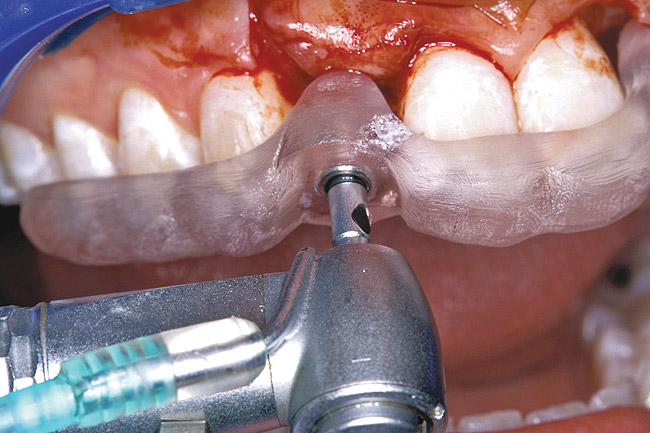

Before the day of surgery, the patient was seen by the orthodontist for the removal of the orthodontic brackets. The patient still was not pleased with the position of the two centrals, and it was determined that this would be addressed after implant placement (Figure 26). The anatomical variations of the crestal tissue and lack of interdental papilla can be appreciated in the close-up views of the right and left sites (Figure 27 and Figure 28). There were no surprises on the day of surgery as all of the decisions were made during the planning phase, before the scalpel ever touched the patient. The occlusal view of the CT 3D model revealed the wider alveolar ridge on the right side and thinner crest on the left side (Figure 29). This was confirmed when the full-thickness mucoperiosteal flaps were elevated, and the underlying bone revealed (Figure 30). The tooth-borne templates were designed to facilitate the drills and drilling sequence specific to the diameters of the predetermined implants (Figure 31). Each template contained an embedded 5-mm long stainless steel tube, which was approximately 0.2-mm wider than each drill (just wide enough to allow for the drills to rotate freely). Once positioned over the natural teeth, the template was secure and offered precision accuracy in transferring the implant locations from the original software-designed plan, allowing the potential for internal and external irrigation (Figure 32).

Figure 30  VIRTUAL PLANNING AND SURGERY The information gained from the 3D model was confirmed when the flaps were elevated.

Figure 30

Figure 31  VIRTUAL PLANNING AND SURGERY A surgical template was derived from the final treatment plan created in the software, which facilitated the drilling sequence and precise location of placement.

Figure 31

Figure 32  VIRTUAL PLANNING AND SURGERY A surgical template was derived from the final treatment plan created in the software, which facilitated the drilling sequence and precise location of placement.

Figure 32